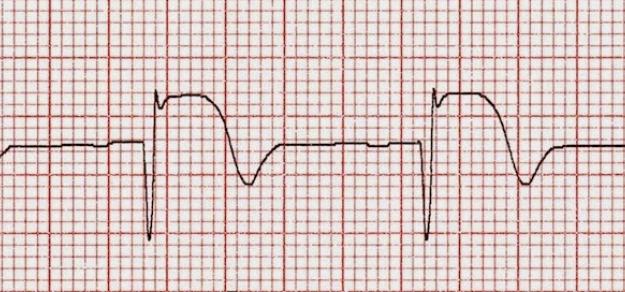

En pacientes con accidente cerebrovascular isquémico agudo tratados con trombolisis, el control intensivo de la presión arterial no fue superior al manejo estándar. The Lancet, 7 de febrero de 2019

Se ha actualizado la guía norteamericana sobre las medidas iniciales frente al accidente cerebrovascular isquémico, de modo de optimizar las posibilidades tempranas de reperfusión y la protección del área de penumbra. Stroke, 24 de enero de 2018

En una gran cohorte de EEUU, una cuarta parte de los pacientes con accidente cerebrovascular isquémico e indicación para tPA-IV no recibieron la medicación. Se asoció con edad avanzada y con el sexo femenino, entre otros factores. Neurology, 14 de septiembre de 2016

Según un estudio observacional, los pacientes con ictus isquémico y lesiones pequeñas en la tomografía computarizada de perfusión podrían no beneficiarse con la trombolisis. Annals of Neurology, agosto de 2016